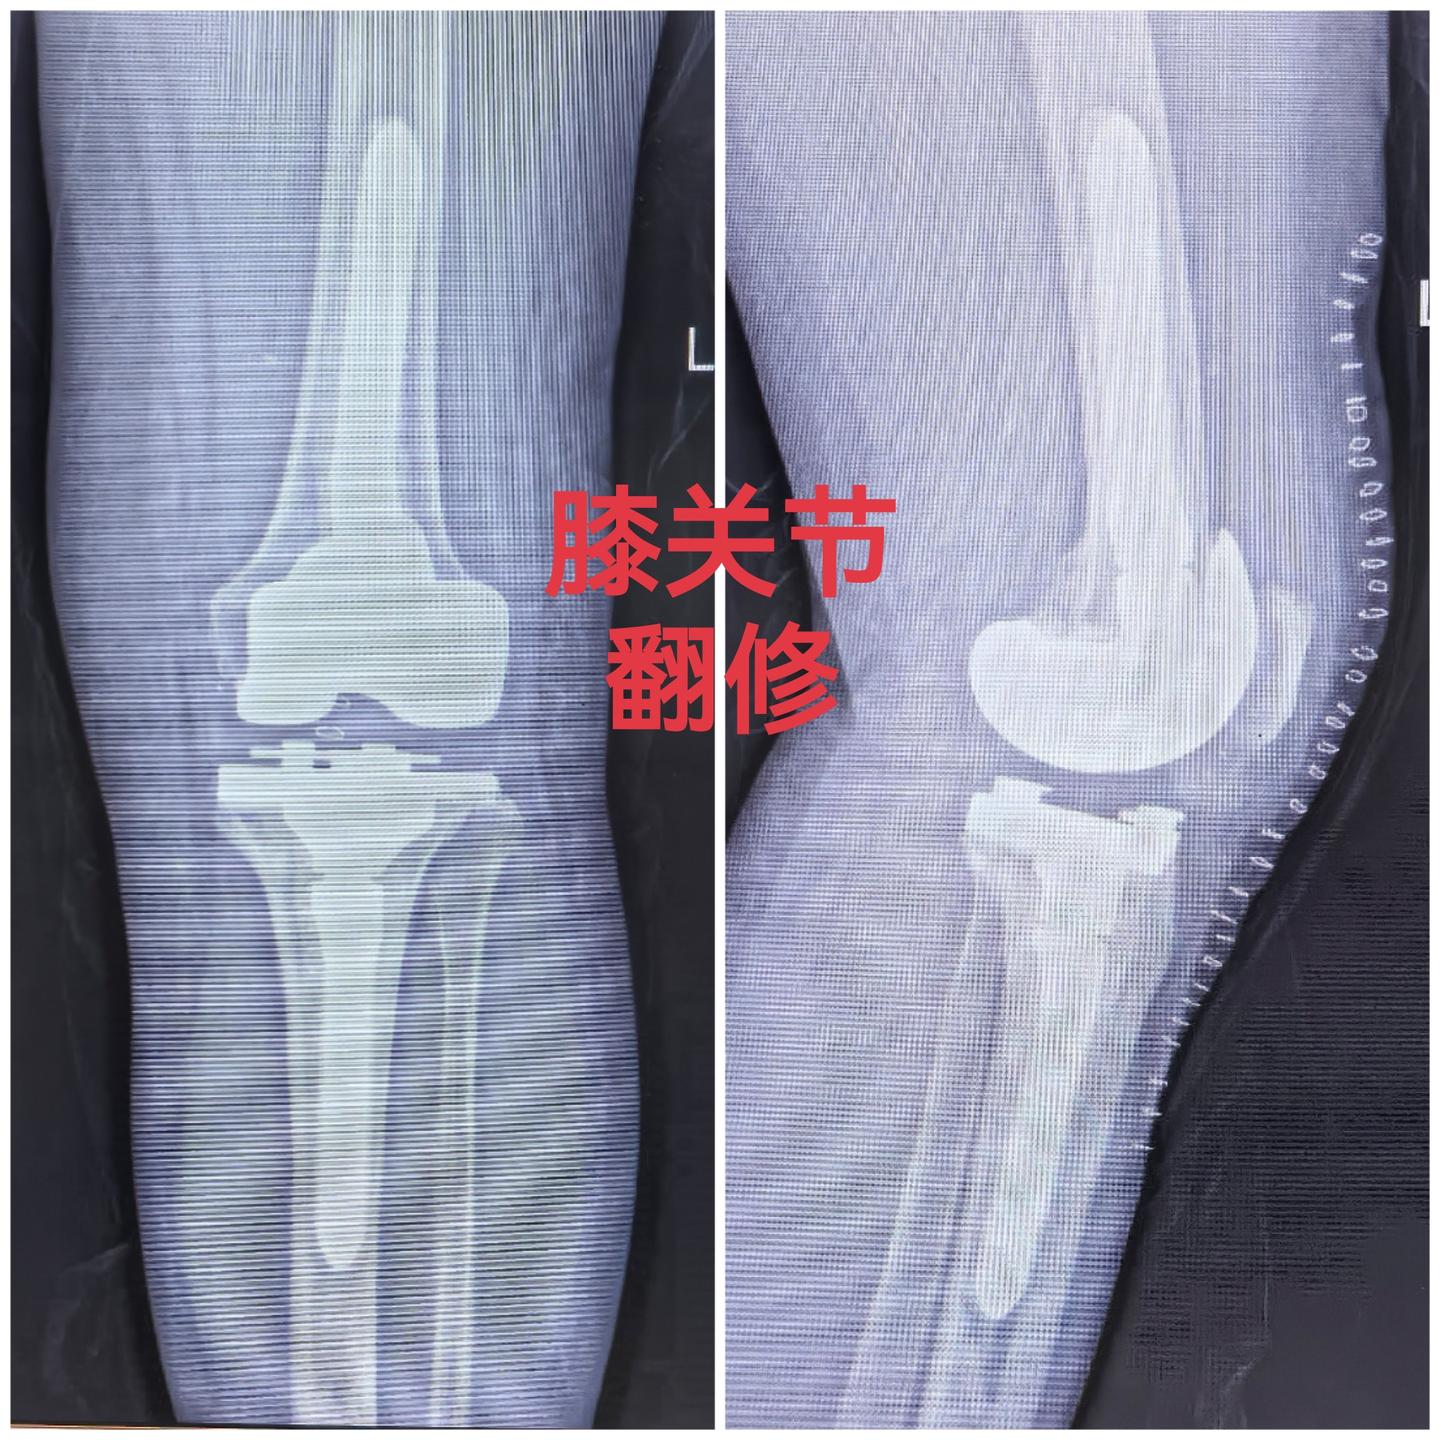

膝关节翻修。80岁老爷子,膝关节置换术后假体松动,一期翻修,再次续命20年🌹